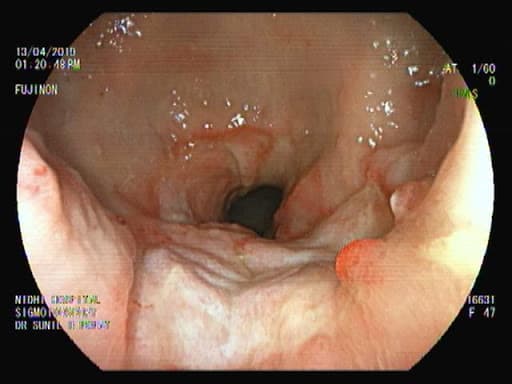

Sigmoidoscopy, or“flexible sigmoidoscopy”, lets a physician examine the lining of the rectum and a portion of the colon (large intestine) by inserting a flexible tube about the thickness of your finger into the anus and slowly advancing it into the rectum and lower part of the colon. This procedure evaluates only the lower third of the colon. Sigmoidoscopy is often done without any sedation, although sedation can be used if necessary.

Various miniaturized tools can be inserted through the scope to help the doctor obtain samples (biopsies) of the colon and to perform maneuvers to diagnose or treat conditions.

Flexible sigmoidoscopy can detect and sometimes treat polyps, rectal bleeding, fissures, strictures, fistulas, and foreign bodies, colorectal cancer, and benign and malignant lesions.

Flexible sigmoidoscopy is not a substitute for total colonoscopy when it is indicated. The finding of a new, abnormally growing polyp during sigmoidoscopy, for example, is an indication for a colonoscopy to search for additional polyps or cancer. Sigmoidoscopy should not be used for polypectomy unless the entire colon is adequately prepared. This procedure should also not be used with cases of diverticulitis, and peritonitis.